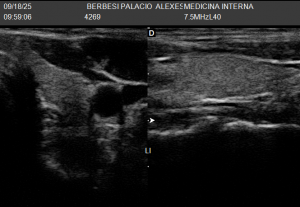

La ecografía tiroidea se realiza observando primero el istmo y luego cada lóbulo (derecho e izquierdo) en planos transversales y longitudinales. Así determinamos el tamaño y la presencia de nódulos, bocios o inflamación. Luego, si es necesario, usamos Doppler para ver el flujo y descartar actividad anormal.

LÓBULO TIROIDEO IZQUIERDO-ECOGRAFIA DE TIROIDES![]() | LÓBULO TIROIDEO DERECHO-ECOGRAFIA DE TIROIDES![]() |